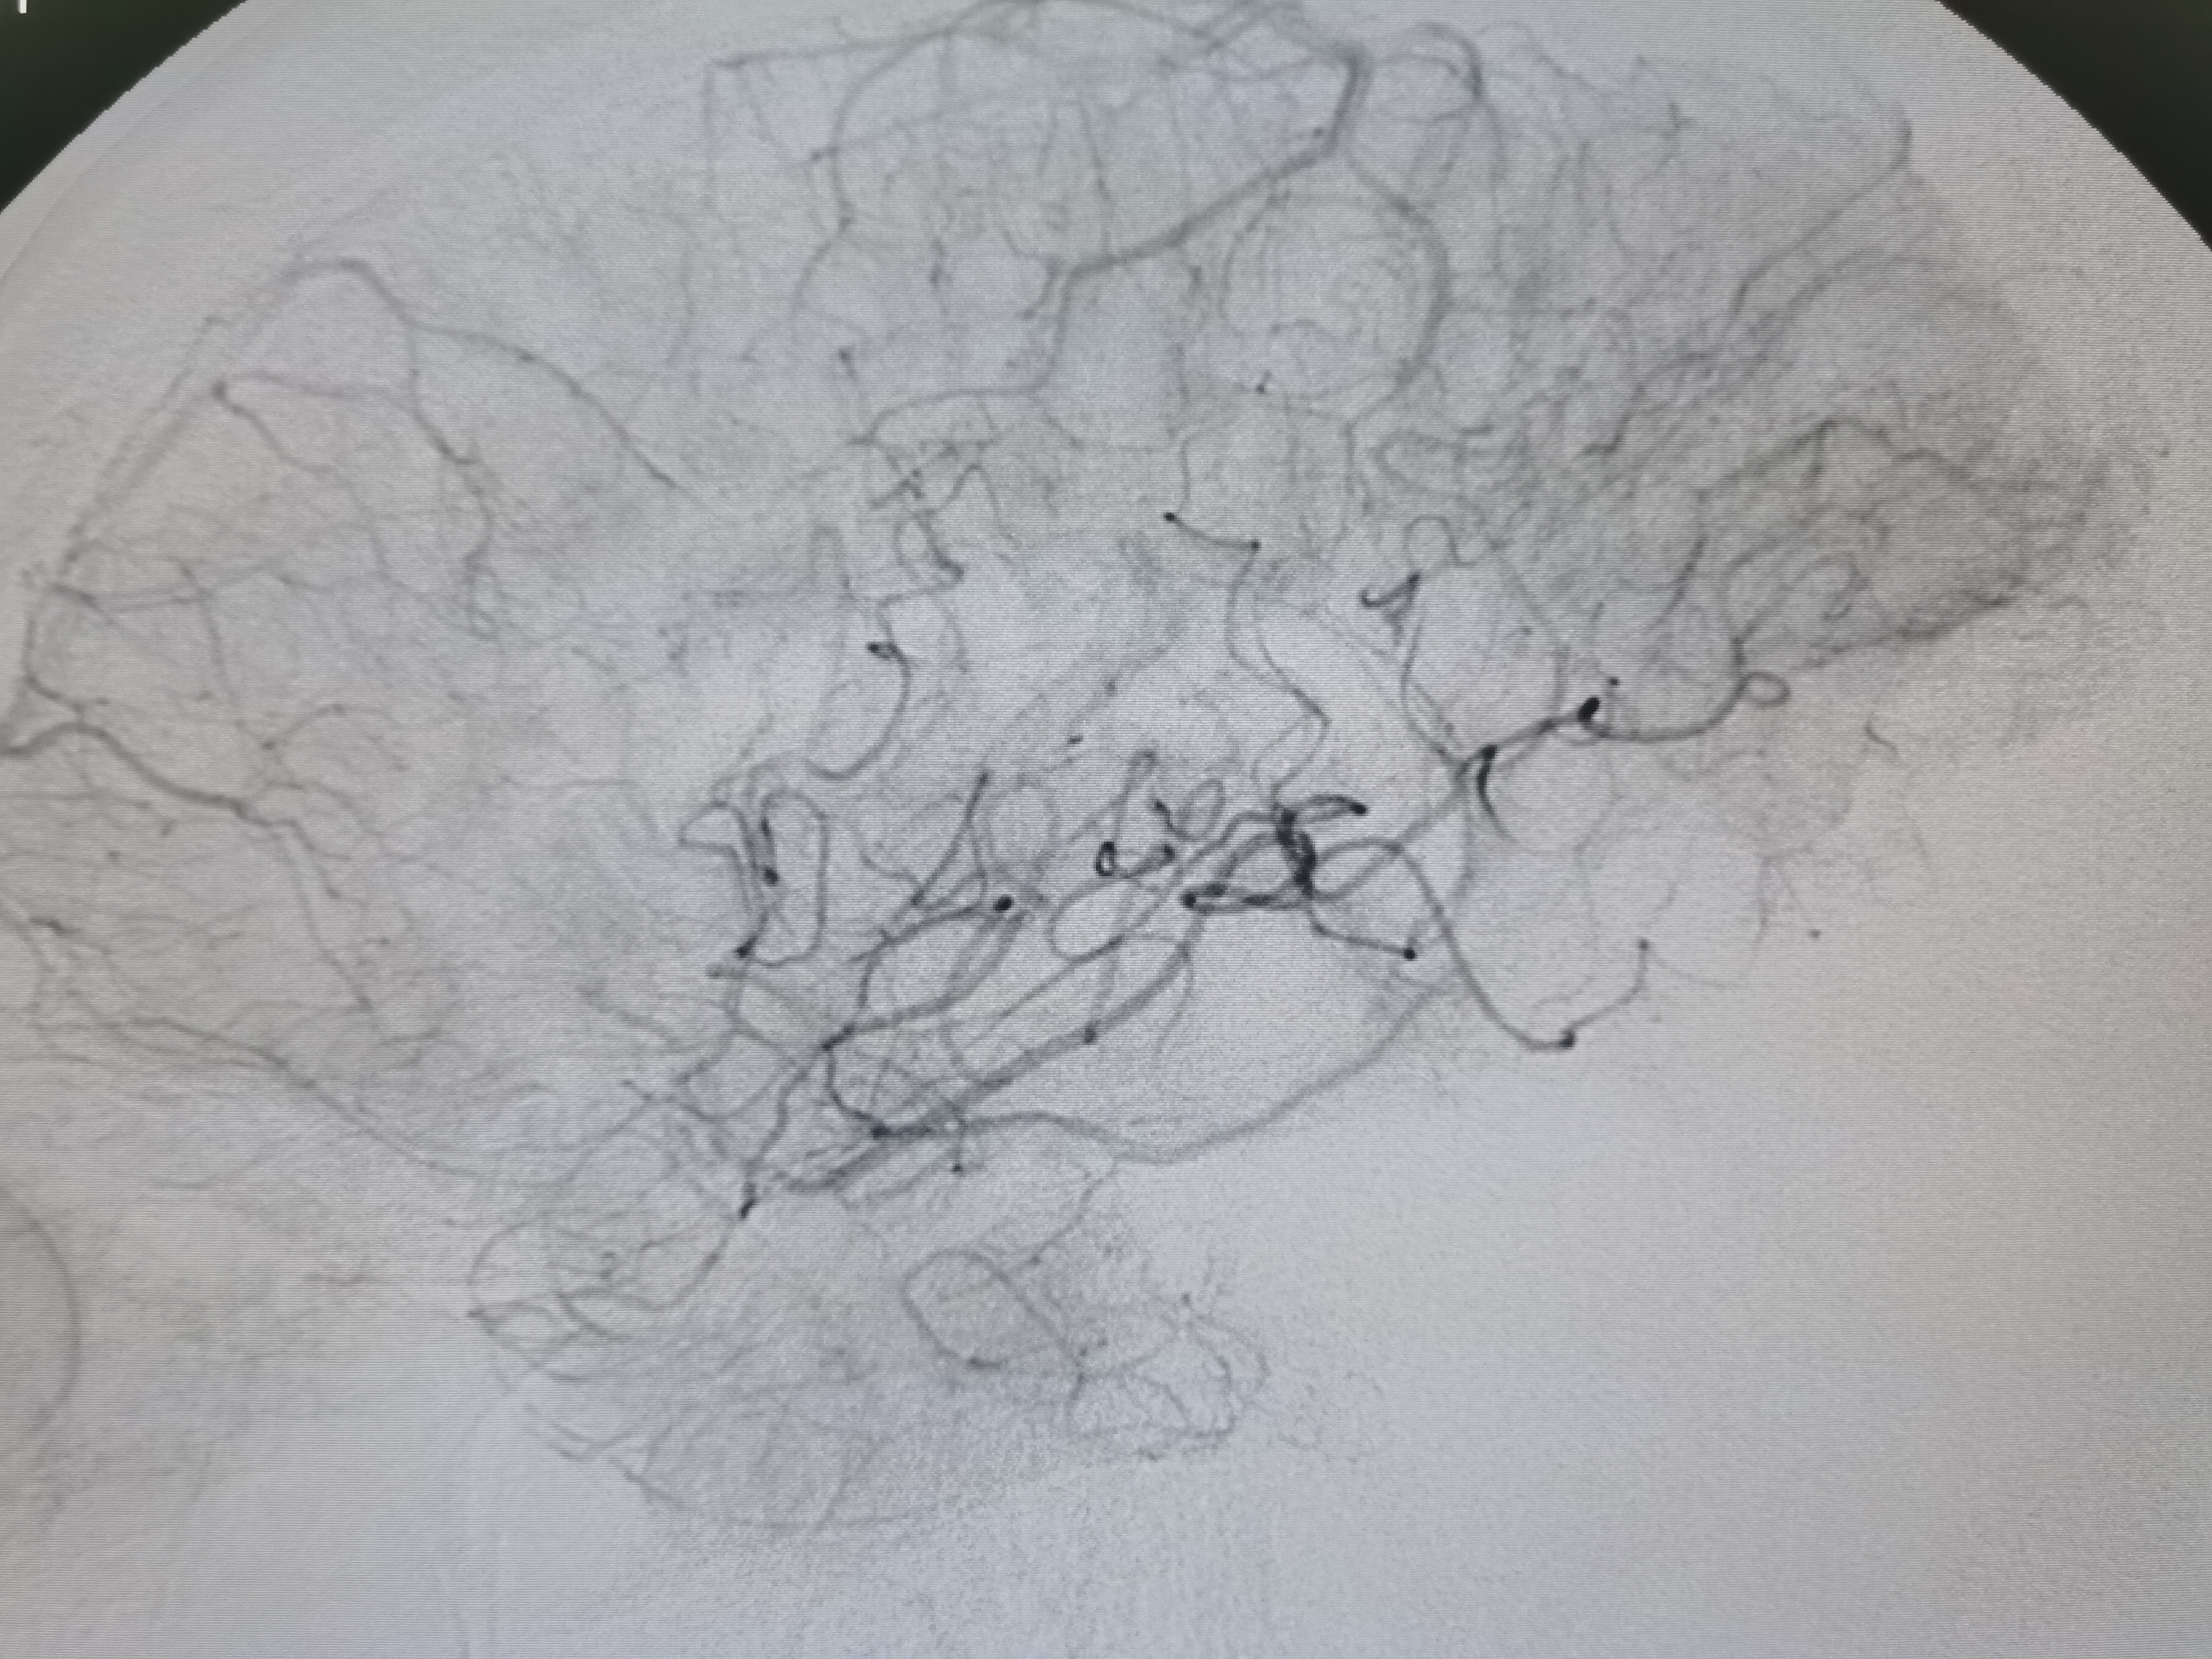

术前术后对比

1、本例患者系因左侧大脑中动脉急性闭塞出现左侧半球梗死,系责任血管。

2、造影评估见左侧大脑中动脉起始段闭塞,但动脉晚期可见远端血管返流显影,考虑闭塞段较短,且为新近闭塞,具备介入治疗指征。

3、球囊扩张后血管狭窄解除,无夹层及弹性回缩,遂未再植入支架,术后继续药物治疗,定期随访。